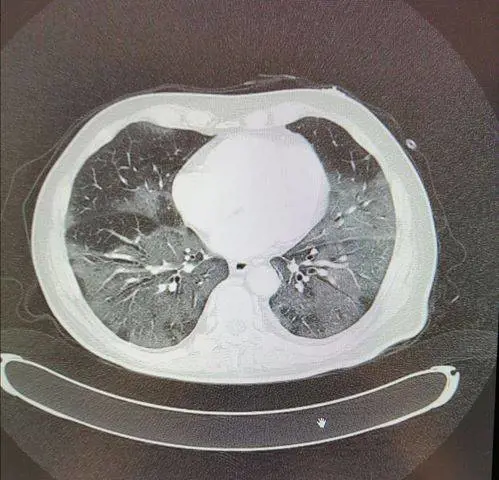

I farmaci per debellare il coronavirus sono pochi, tanto dipende da come reagisce il nostro organismo. La speranza è che riesca il nostro fisico a debellare il virus da solo. Macchini lo dice senza peli sulla lingua. Va poi sul tecnico spiegando perfettamente le differenze tra una normale influenza e il Covid-19. E fa paura leggere, ma almeno ci si rende conto di cosa stiamo affrontando, perché in diversi casi il coronavirus “arriva direttamente negli alveoli dei polmoni e li infetta rendendoli incapaci di svolgere la loro funzione. L’insufficienza respiratoria che ne deriva è spesso grave e dopo pochi giorni di ricovero il semplice ossigeno che si può somministrare in un reparto può non bastare”.